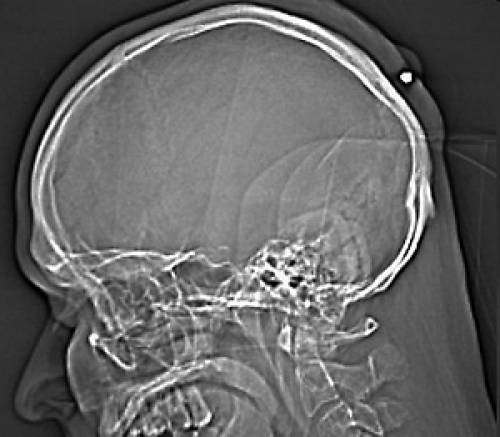

這名男子向警察透露,他記得頭部確實遭到衝擊,並且後來也出現劇烈疼痛,不過他又不是那種樂於看病的人,所以沒有到醫院就診。直到最近他感覺頭後部出現一個腫塊,才去醫院檢查。透視結果發現,在他頭部皮層的下面有不明物體,醫生通過手術發現竟然是一顆子彈,所幸的是子彈沒有穿透他的頭骨。據環球時報

透視結果發現子彈位置如圖